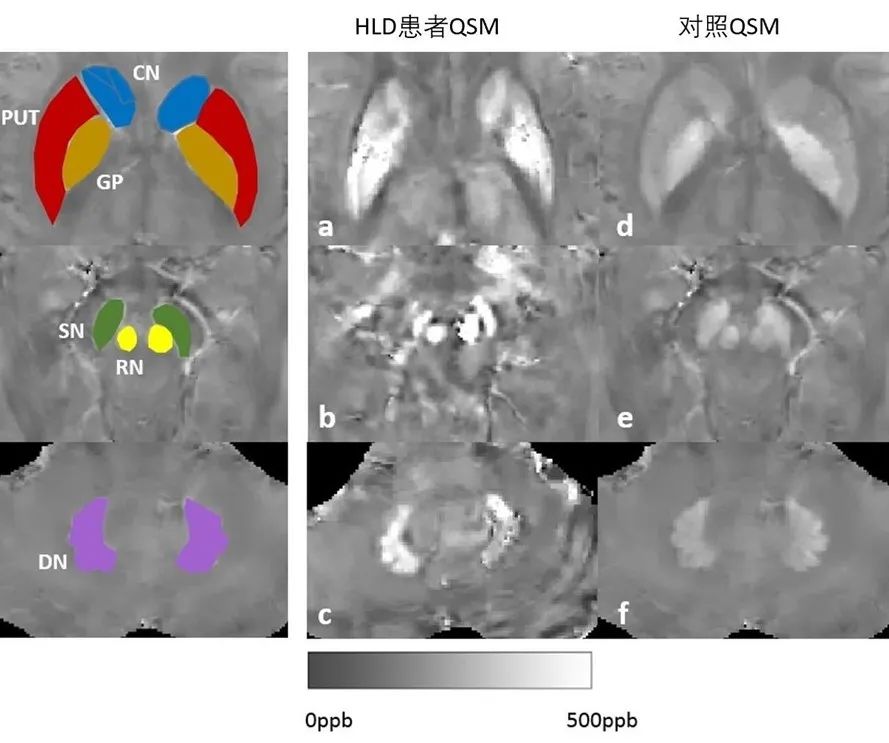

肝豆状核变性,是一种铜代谢障碍相关的常染色体隐性遗传疾病。其发病机制为 ATP7B 基因突变,导致铜转运 P 型 ATP 酶结构和功能异常,铜在肝脏、脑、角膜等部位异常沉积,造成相应器官的损伤。作为铁氧化酶的铜蓝蛋白合成减少,同时也导致患者体内铁代谢障碍。根据近期大规模全基因组测序研究结果,ATP7B 杂合突变携带率约为 1/40,该病预计发病率为 1/7000,远高于其他神经系统遗传疾病。如何能利用影像学方法早期精准诊断 HLD、对体内铜铁分布进行动态观察、根据患者铜铁蓄积情况制定个体化治疗方案,是目前亟待解决的问题。本研究通过对肝豆状核变性患者脑深部灰质核团的磁化率和 R2*图的定量和定性评估来区分肝豆状核变性患者和健康对照组,并且评估上述两者对于在诊断肝豆状核变性时的敏感性。研究发现定量磁化率和 R2*可以有效区分不同的病变类型。磁化率和 R2*值在肝豆状核变性患者多种深部核团中显著高于正常对照组。磁化率值在黑质区域有最大的曲线下面积(0.888)。在尾状核 (r = 0.757, P = 0.011)、壳核 (r = 0.679, P = 0.031)、红核 (r = 0.638, P = 0.047) 中,统一肝豆状核变性评估量表值和磁化率值呈正相关,而在尾状核 (r = 0.754, P = 0.012) 中,其与 R2*值也呈正相关。

本研究是利用定量磁化率成像和 R2*图对肝豆状核变性患者脑深部核团金属沉积开展相关分析,定性分析发现,HLD 患者豆状核有三种类型的病变。QSM 在区分 HLD 患者不同类型的病变方面表现良好,为 HLD 中不同类型的病变的诊断提供了辅助信息。在大多数深部核团中,QSM 在区分 HLD 患者与健康对照组方面比 R2*更准确。在 HLD 患者与健康对照组的对比中,中脑核团(黑质和红核)在 QSM 和 R2*中表现出的差异较基底节核团(尾状核、壳核和苍白球)和小脑核团(齿状核)更加明显。患者临床症状评分分数(统一肝豆状核变性评分量表,UWDRS)与 HLD 受试者尾状核的磁化率值之间存在显著的正相关关系。QSM 或 R2*值与其他临床指数没有相关性,特别是尿铜和血清铜蓝蛋白。进而,我们认为基于 3.0 T MRI 的定量磁化率成像是评估肝豆状核变性患者脑深部灰质核团中金属沉积情况的有效手段。